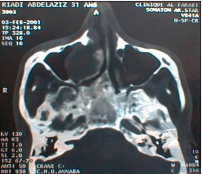

All patients were submitted to diagnostic anamnesis approach, facial examen, nasal endoscopy and computed tomography (CT) (Figure 1).

Figure 1 CT axial plane: right maxillary mucocele (medial wall).

Figure 1: CT axial plane: right maxillary mucocele (medial wall).

Symptomatology is not specific. We can found nasal obstruction, rhinorrhea, epistaxis, facial pain, facial deformation, proptosis, peri orbital swelling, epiphora, palatal deformity, dental problems or radiologic discovery. Nasal endoscopy shows anomalies of lateral nasal way (disformed). Computed tomography in the axial and coronal plane gives a reliable extension balance, the sinus is enlarged with wall blowed reduced or interrupted. Its contents isodense or hypodense and no contrast enhancement, unless infected.